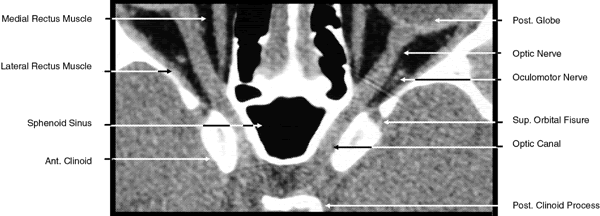

2D CT imaging is most frequently performed in the axial plane (Fig. 2). The bony anatomy of the orbit, optic canal, and intracranial cavity determines the exact orientation of this plane to provide the best visualization of both bone and soft tissue. The bony orbit is shaped like a quadrilateral pyramid lying on its side and with its base facing anteriorly. The medial orbital walls are almost parallel, although they tend to converge toward the midline in their posterior aspect. The lateral orbital walls diverge at approximately 45 degrees to the midline. The orbital axis is about 23 degrees divergent from the midline. The orbitomeatal line (Reid's baseline or the Frankfurt-Virchow line) is an important radiologic landmark for imaging the orbital structures. It is a line that extends from the upper margin of the external auditory meatus to the inferior orbital rim. The orbital floor is at approximately a -20-degree angle with this line, and the optic canal is at approximately a -30-degree angle with this line. Axial scans of the orbit are performed parallel to the orbitomeatal line, in contrast to axial scans of the intracranial contents, which are performed in a plane parallel to the orbital roof, which is at a + 30-degree angle to this line. The optic chiasm is also best imaged in a plane parallel to the orbitomeatal line. Although both the optic canal and nerve can be adequately visualized with axial scans parallel to this plane, scans of these structures are more precisely performed if the image plane is at a -30-degree angle to this line with the globe in upward gaze. This straightens the nerve and places its axis in the same plane as the canal. The optic canal of infants and young children is at approximately a -20-degree angle with the orbitomeatal line, and in these age groups the scanning angle is appropriately modified for precise imaging of this structure. For orbital scans a 3-mm slice thickness is usually employed; for scanning the optic nerve and canal, a 1.5-mm slice thickness is recommeded to image these structures completely (Fig. 3). Thin-slice technique is helpful in reducing the effects of partial volume averaging, thus improving image resolution of small-diameter structures such as the optic nerve. In contrast, axial scans of the intracranial contents are usually 5- or 10-mm thick slices, although thinner slices are often used when imaging structures such as the cavernous sinus, suprasellar cistern, pituitary gland, and optic chiasm. Generally, the radiation dose associated with thin-cut CT imaging is 30 mGy (using 3-mm slice increments) to 80 mGy (using consecutive 1.5-mm scans), which is considerably less than complex motion tomography of the facial area and similar to standard plane film head scans.

Fig. 2. Axial computed tomography scan at the level of midorbit.

Fig. 3. Axial computed tomography scan of the orbital apex and optic canal.

The globe is shown in Figure 12. The orbit and periorbital structures are shown in Figures 13 through 16, and the optic canal is shown in Figures 17 through 26. The cavernous sinus and optic chiasm are shown in Figures 27 and 28, and the posterior visual pathway and cranial nerves are shown in Figures 29 through 33.

Fig. 22. Axial images at the level of inferior orbit. A. Computed tomography scan. B. T1-weighted magnetic resonance imaging.

Fig. 23. Axial images at the level of midorbit. A. Computed tomography scan. B. T1-weighted magnetic resonance imaging.

Fig. 24. Axial images at the level of superior orbit. A. Computed tomography scan. B. T1-weighted magnetic resonance imaging.

Fig. 25. Axial images at the level of tendon of the superior oblique. A. Computed tomography scan. B. T1-weighted magnetic resonance imaging.

Fig. 27. Coronal images through cavernous sinus and optic chiasm. A. T1-weighted magnetic resonance imaging through anterior chiasm. B. Computed tomography image through anterior chiasm. C. Computed tomography image through posterior chiasm. D. Computed tomography image through optic tract.

Fig. 28. Axial computed tomography image with contrast medium through cavernous sinus and pituitary gland.

The superior orbital fissure separates the orbital roof from the lateral orbital wall and the lesser and greater wings of the sphenoid bone (see Figs. 13 and 14). The common tendinous ring (annulus of Zinn) of the extraocular muscles and the spine for the insertion of the lateral rectus muscle separates the fissure into a thin superolateral portion and a wide inferomedial portion (see Fig. 21). The fissure is approximately 22 mm long, and its superior end is 30 to 40 mm from the frontozygomatic suture.48 Directly posterior to the fissure are the middle cranial fossa and temporal lobe. Passing through the superior portion of the fissure above the tendinous ring are the lacrimal (cranial nerve V), frontal (cranial nerve V), and trochlear (cranial nerve IV) nerves, the superior ophthalmic vein, and the recurrent lacrimal artery. Passing within the ring are the superior division of the oculomotor nerve (cranial nerve III) and the abducens nerve (cranial nerve VI) laterally, the nasociliary nerve (cranial nerve V) and the inferior division of the oculomotor nerve medially, and the sympathetic root of the ciliary ganglion and the inferior ophthalmic vein, which on occasion may pass below the ring. The tendinous insertions of the lateral and inferior rectus muscles form the superior, lateral, and inferior portions of the ring in the area of the superior orbital fissure. There is no muscle tendon medial to the fissure. The medial border of the fissure is formed by a strut of bone from the lesser wing of the sphenoid bone, which separates it from the optic canal.